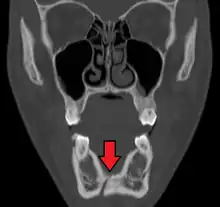

Towne's view of a bilateral condyle fracture. White arrow is a fracture on the neck of the condyle. Black arrow shows the condyle pulled to the medial. The same injury can be seen on the opposite side